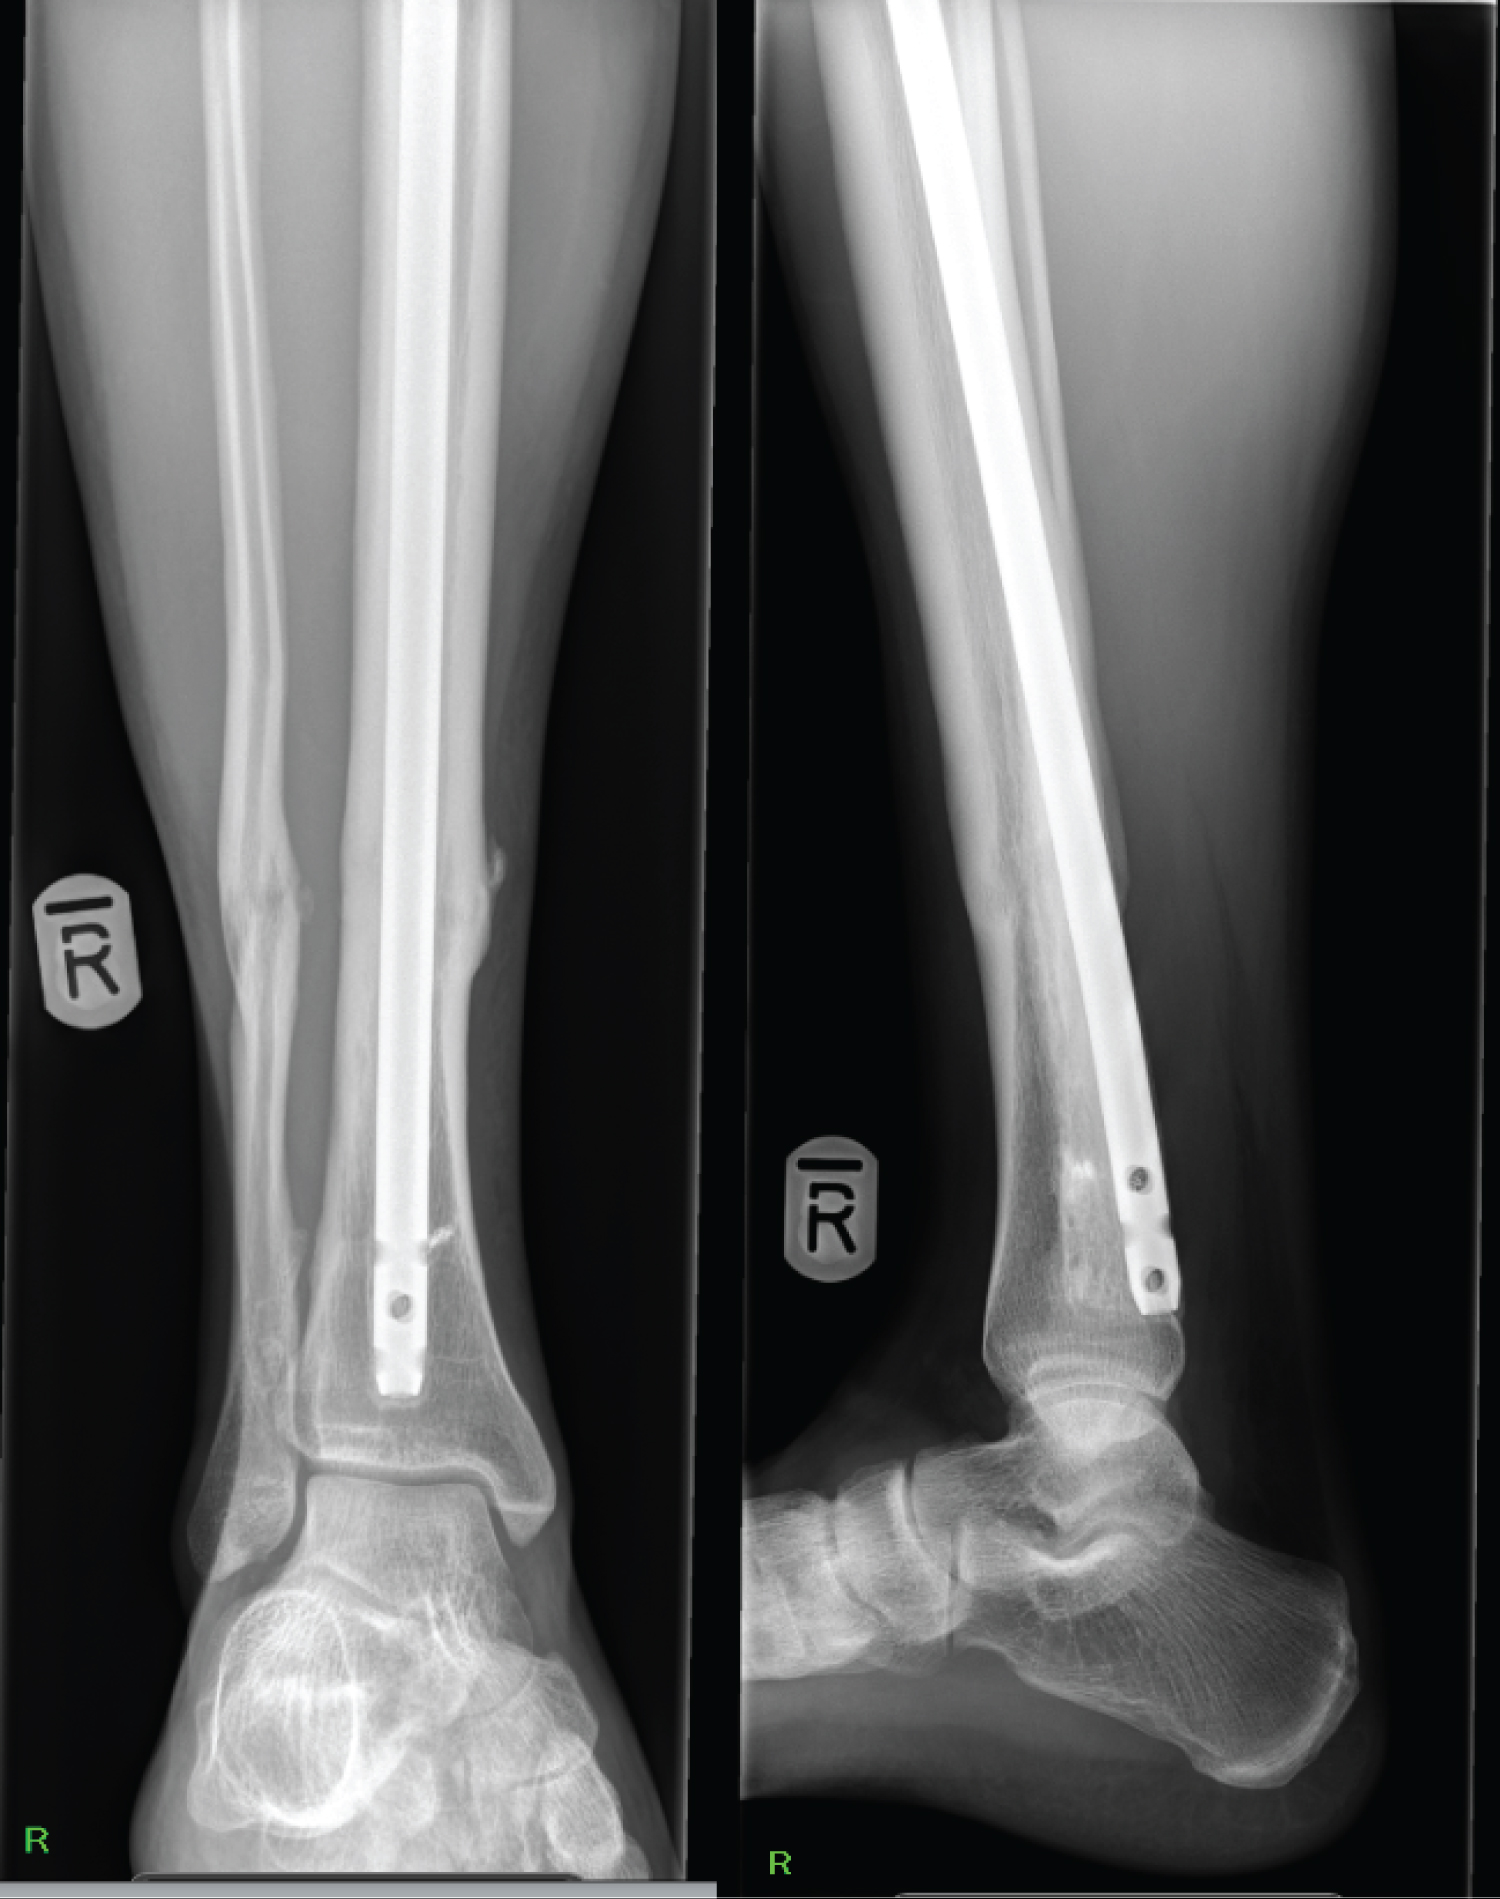

A 20 year old man suffered a closed, oblique fracture of his right tibial diaphysis at the junction of the middle and distal third with an associated fibula fracture whilst playing football (Figure 1). His tibia was stabilised with an antegrade, reamed, intramedullary nail and proximal and distal bolts, on a planned trauma list. The position on intraoperative fluoroscopy and post-operative radiographs show an appropriate reduction and position of the nail (Figure 2). Immediate weight bearing as pain allows was commenced post-operatively and after clinical and radiographic union, was permitted to return to sport and work as a crane driver.

Figure 2: AP + Lateral X-ray 4 weeks post ORIF. View Figure 2